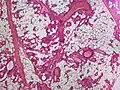

.jpg.webp) Small vessels in adipose tissue

Small vessels in adipose tissue.jpg.webp) Small vessels in adipose tissue

Small vessels in adipose tissue Small vessels in adipose tissue

Small vessels in adipose tissue Small vessels in adipose tissue

Small vessels in adipose tissue The vessels typically contain hyaline or fibrin (pictured) thrombi[3]